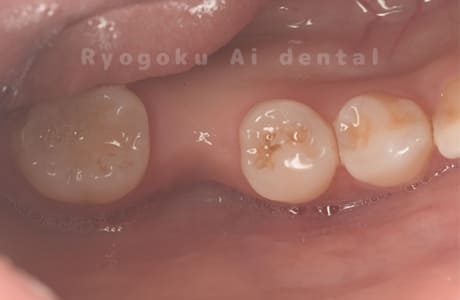

Case07

- 原因

- 右下6番歯根破折

-

- 治療内容

- インプラント治療

- 治療費用

- 約600,000円

右下の腫れが治らないとの事でご来院された患者様です。歯が割れていたため、抜歯を行い、骨に代わるお薬を入れ、インプラントを埋入致しました。経過良好で大変満足していただけました。

<リスク・副作用>

治療後、痛みや違和感、出血、腫れなどが出る事があります。喫煙者、糖尿病などの方の場合、歯が生着しない場合があります。